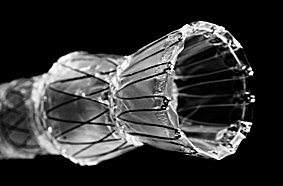

CMR VERSIUS - LEIKKAUSROBOTTIEndoskopia instrumentitEndoskopia- ja instrumentaatiopesuEndoskopialaitteetFiksaatiotuotteetGastrokirurgiaGynekologiaHemostaatitIholiimatkirurginen liimaKNKLaparoskooppinen kirurgiaMuut tuotteetNEUROKIRURGIAObstetriikka / obstetriaOrtopediaStapleritStentitSurgitel luupit, luuppivalot ja kameratUrologia